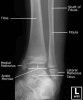

소아 발목의 X-ray2017-02-26카테고리 103원본 보기 Ankle Paediatric Protocol : AP, Lateral Ankle AP view Ankle Mortise view Ankle Lateral view ← 이전 글소아 무릎, 아래 다리의 X-ray다음 글 →발목관절 골절(Salter-Harris fracture)같은 카테고리 글2017-02-25소아 무릎, 아래 다리의 X-ray2017-02-18소아의 골반, 고관절, 대퇴골의 X-ray2017-02-14손목 성장판 골단판 골절(Epiphysiolysis fracture)← 전체 글로 돌아가기